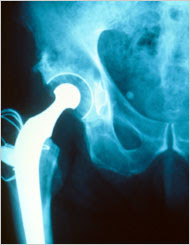

An x-ray of affected joints will show a loss of the joint space. In advanced cases, there will be a wearing down of the ends of the bone and bone spurs.

Severe cases of OA might need surgery to replace or repair damaged joints. Surgical options include:

- Total or partial replacement of the damaged joint with an artificial joint (knee replacement, hip replacement, shoulder replacement,ankle replacement, elbow replacement)